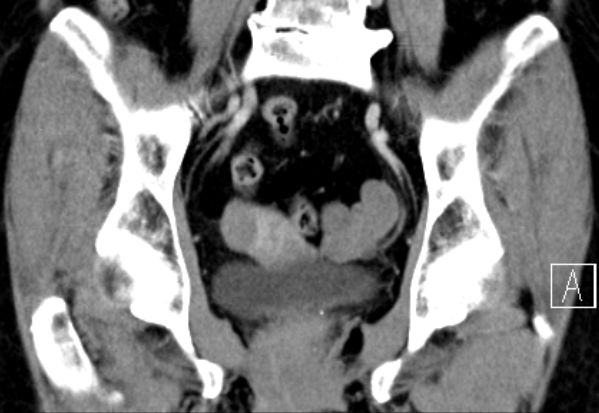

| Diagnostik | 70-jährige Frau mit einer RF des linken Adnex. Histologisch adulter Granulosazelltumor FIGO Ia.![]() |

| Morphologie | meistens unilaterale, solide (auch multizystisch) mit grauweißer oder gelblicher Schnittfläche. | |||